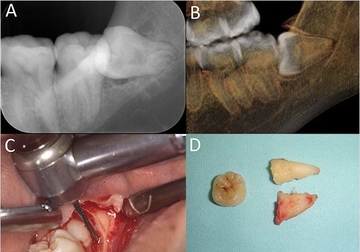

オーラルエステです親知らず

どの歯が親知らず?

歯茎が半分被っている歯、斜めになってる歯

骨の中で逆さまの歯

骨の中で真横の歯

歯を削る道具が、親知らずまで届きにくくて、完全にむし歯を取り切る事ができなかったりします。親知らずの治療はかなり難しいです。一枚目写真の様に真っ直ぐに生えている歯ならば、器具が届けば治療できます。

まとめ